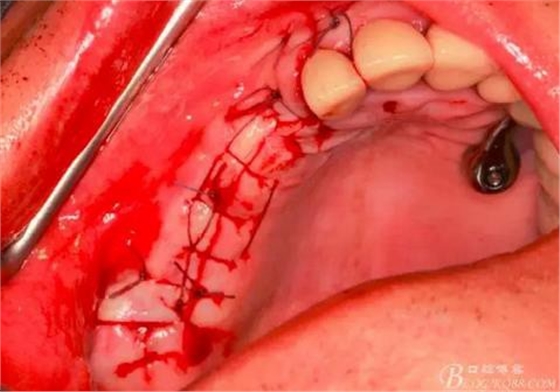

14,15牙位植入兩顆植體,6,7牙位骨高度嚴(yán)重不足,且骨密度低,無法給植體提供良好的初期穩(wěn)定性,需二期植入。13牙位骨寬度不足,沒有植骨、植植體,修復(fù)時(shí)用后面4顆連冠加一顆3的游離臂是沒有問題的。當(dāng)然這里我們不去討論這個(gè)方法的合理性,我們今天的話題是改良式外提升技術(shù)的應(yīng)用。